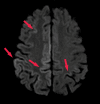

Neurodegenerative diseases are a devastating group of disorders that can be difficult to accurately diagnose. Although these disorders are difficult to manage owing to relatively limited treatment options, an early and correct diagnosis can help with managing symptoms and coping with the later stages of these disease processes. Both anatomic structural imaging and physiologic molecular imaging have evolved to a state in which these neurodegenerative processes can be identified relatively early with high accuracy. To determine the underlying disease, the radiologist should understand the different distributions and pathophysiologic processes involved. High-spatial-resolution MRI allows detection of subtle morphologic changes, as well as potential complications and alternate diagnoses, while molecular imaging allows visualization of altered function or abnormal increased or decreased concentration of disease-specific markers. These methodologies are complementary. Appropriate workup and interpretation of diagnostic studies require an integrated, multimodality, multidisciplinary approach. This article reviews the protocols and findings at MRI and nuclear medicine imaging, including with the use of flurodeoxyglucose, amyloid tracers, and dopaminergic transporter imaging (ioflupane). The pathophysiology of some of the major neurodegenerative processes and their clinical presentations are also reviewed; this information is critical to understand how these imaging modalities work, and it aids in the integration of clinical data to help synthesize a final diagnosis. Radiologists and nuclear medicine physicians aiming to include the evaluation of neurodegenerative diseases in their practice should be aware of and familiar with the multiple imaging modalities available and how using these modalities is essential in the multidisciplinary management of patients with neurodegenerative diseases.©RSNA, 2020.